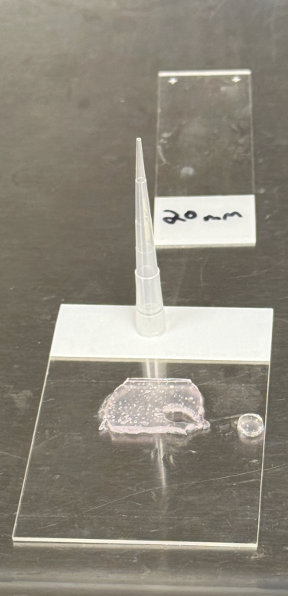

Masters work - validation of rotator cuff repair patch with stem cell implanted hydrogel.

Implanting cells into hydrogel and performing live/dead stain assay.